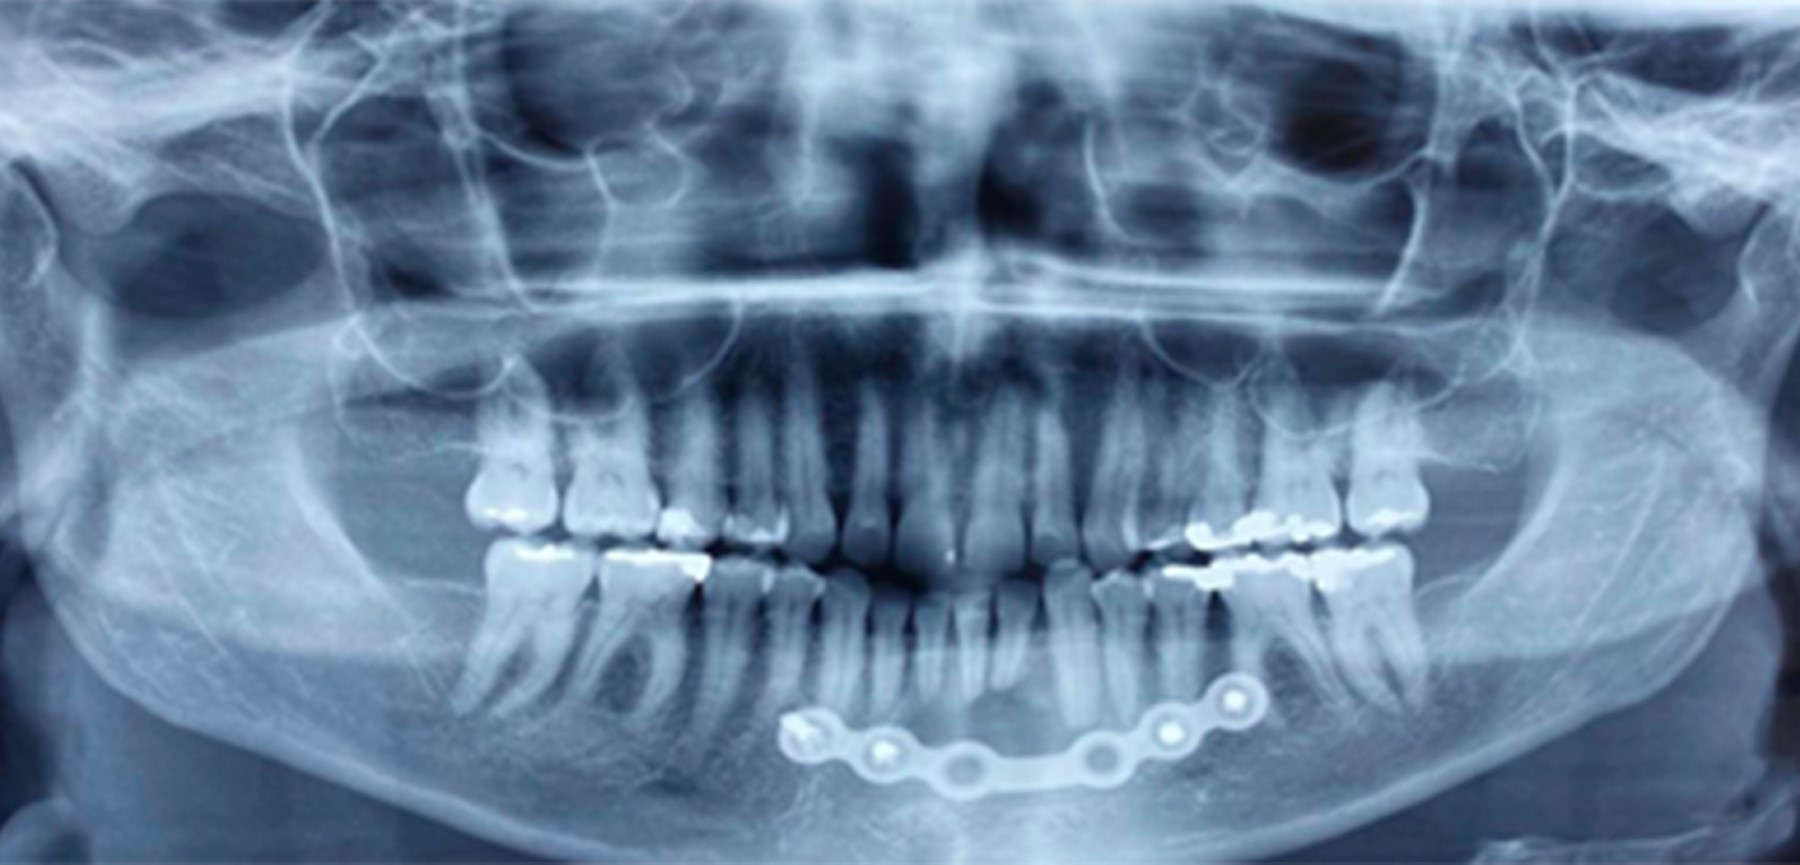

Se optó por una fijación interna estable con una placa de reconstrucción Stryker® de tipo 2,4 con el fin de prevenir el riesgo de fractura patológica en el postoperatorio, debido a la fragilidad ósea de la cortical lingual, y porque la lesión se encuentra en el arco central mandibular, generando fragilidad a la región debido a las fuerzas musculares vectoriales y a la torsión (Figura 5).

En la radiografía panorámica de control postoperatoria a los cuatro meses se observa una fijación interna estable y una adecuada cicatrización ósea (Figura 6).